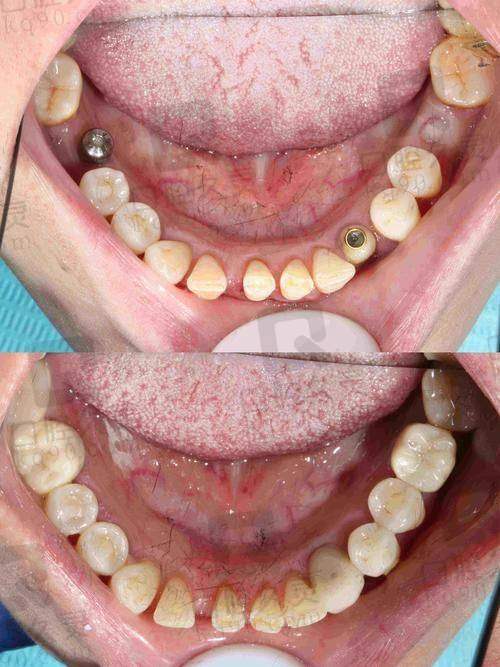

手术采用微创种植技术,减少传统“翻瓣手术”的不适感,术后修复快、肿胀小、几乎不影响正常生活节奏,非常适合怕痛星人或老年人。

不仅如此,医院口腔美学修复与种植体融合设计理念,确保做出的牙既能“啃骨头”,又能“上镜好看”。这才是高配种植体验!

西宁诺贝尔的服务模式也让小编“狠狠地点个赞”——从术前检查、术中操作,到术后复查和保养指导,院内会制定个人数字口腔档案,医生全程跟踪回访,系统护理让种植牙的使用寿命更长达15年以上!